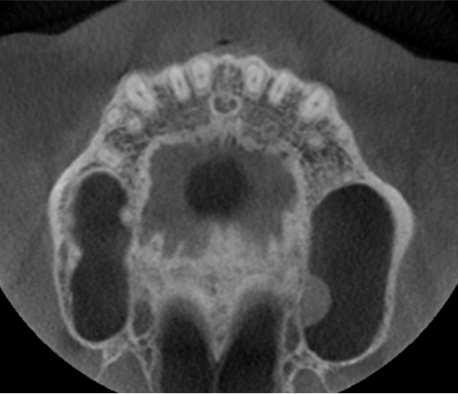

33) Identify the type of CBCT image. (1 mark)